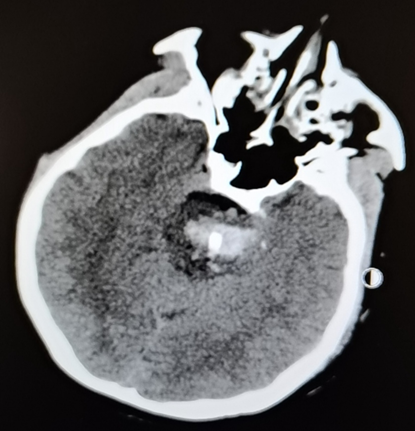

患者赵某,女性,51岁,家住吉林省珲春市。7月24日晚突发意识障碍,送至当地医院,经头部CT后诊断为脑干出血。随后,患者出现双瞳散大、呼吸停止等症状,濒临死亡。患者家属知晓吉林大学中日联谊医院神经外科在脑干出血的患者抢救方面有丰富经验,患者家属于7月25日下午16:00将患者转诊至吉林大学中日联谊医院。特殊情况采用特殊手段,在患者抵达医院时,以高宇飞主任为首的医疗团队在医院多个科室协助下,及时为患者开通绿色通道,将患者紧急收治神经外科NICU维持生命体征治疗。张金男副教授、陈广永主治医师为患者安装立体定向头架,人工呼吸囊辅助下行头部CT检查。整个科室紧急为患者制定详细的手术计划。当晚20:00,手术准时开始,在神经外科手术机器人的辅助下,将引流管经患者左侧小脑精准植入脑干血肿腔,引流管侧孔直通四脑室,在引流血肿的同时,引流四脑室脑脊液,直接减少脑干周围的压力。患者术后恢复自主呼吸。7月27日凌晨,患者意识恢复,自主睁眼,手术圆满成功。